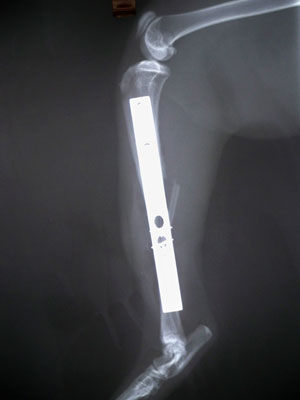

Γάτος 12 μηνών με συντριπτικό κάταγμα μεσότητας κνήμης και κάταγμα περόνης. Παλαιότητα κατάγματος περίπου 2 βδομάδες. Έγινε ανάταξη των 2 μικρών κομματιών με 2 σύρματα. Ακολούθησε ανάταξη των καταγματικών άκρων με πλάκα 2.7mm. Τοποθετήθηκαν 5 κοχλίες στο κεντρικό κομμάτι και 3 στο περιφερικό (2.7mm).

Χειρουργοί : Πούπαλος Γιώργος, Σιδεράς Δημήτρης